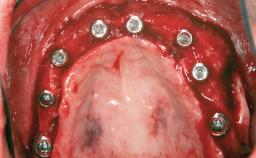

A 47-year-old woman who had suffered from aggressive periodontitis requiring a number of periodontal interventions over more than 10 years was referred by her general dental practitioner and periodontologist for bone augmentation and implant therapy. Her failing dentition had already been scheduled for extraction. The patient expressed a desire for implant-supported fixed restorations and esthetic improvement of her lower face. She had agreed to consult with a maxillofacial surgeon after the referring dentist had suggested bone augmentation. An initial examination by the maxillofacial surgeon revealed mobility of all residual teeth in a patient who was very unhappy with the function of her removable partial dentures. Due to periodontally migrated flaring teeth and loss of occlusal support, the vertical dimension of occlusion was dramatically reduced. The patient was displeased with her lower face because of deepened nasolabial, commissural, and supramental folds.

# of Implants 14

Type of Implants Two-Piece

Bone Augmentation Horizontal|Sinus Floor Elevation|Staged|Vertical